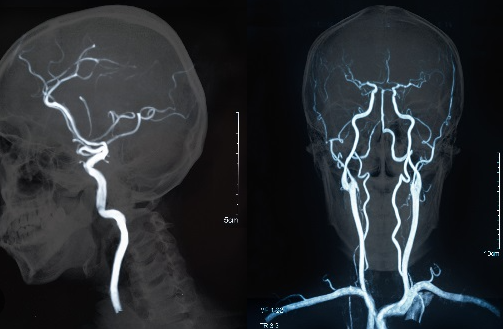

뇌졸중은 뇌혈관이 막혀서 혈액이 뇌로 제대로 공급되지 않거나, 뇌혈관이 파열되어 뇌에 출혈이 일어나는 질병입니다. 뇌졸중은 뇌손상, 마비, 어려움 등 다양한 증상을 유발할 수 있습니다.